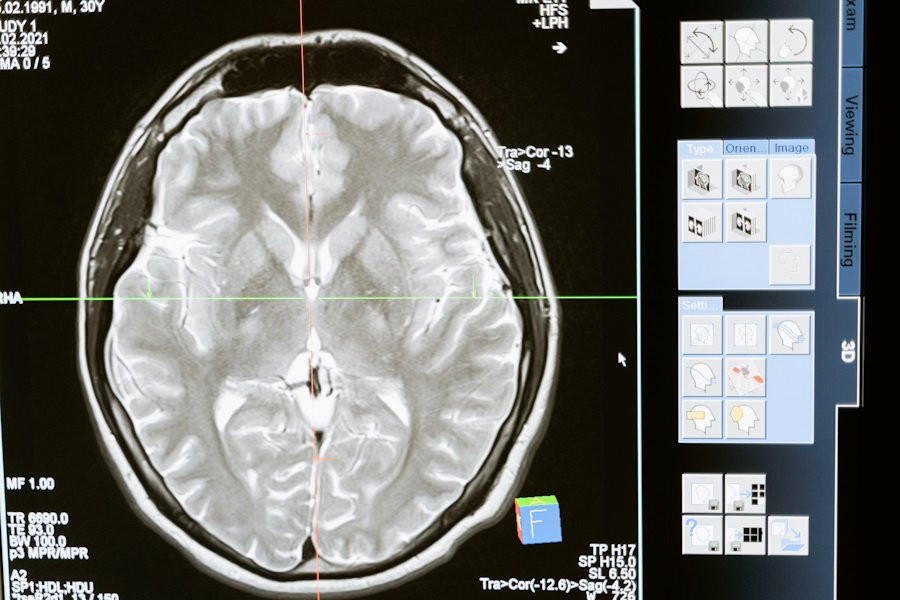

Учёные выяснили роль дофамина в краткосрочной и долгосрочной памяти

Учёные из Стэнфордского и Йельского университетов недавно опубликовали исследование, в котором изучили, как кратковременная и долговременная память взаимодействуют у животных, используя плодовых мух (дрозофил) в качестве модели, сообщает Nature.

В повседневной жизни животные принимают решения, основываясь на врождённых инстинктах и прошлом опыте. Однако до сих пор было непонятно, как врождённые реакции на определённые сигналы взаимодействуют с информацией, которую животное уже усвоило, и как это влияет на процесс запоминания. В новом исследовании учёные обнаружили, что в мозге дрозофил существуют связанные между собой механизмы кратковременной и долговременной памяти, которые управляются сигналами дофамина — вещества, играющего ключевую роль в передаче информации в мозге.

Исследователи использовали специальную технику, позволяющую видеть, как реагируют нервные клетки у живых мух в процессе обучения. Они выяснили, что различные группы дофаминовых нейронов по-разному кодируют врождённые и усвоенные сигналы, такие как запахи и связанные с ними приятные или неприятные ощущения. На ранних стадиях обучения эти сигналы помогают формировать кратковременные воспоминания. Однако по мере продолжения обучения изменяется работа нейронов, и это позволяет формироваться более стойким, долговременным воспоминаниям.

Моделирование показало, что эти процессы могут быть схожи и у других видов, включая человека. Данное исследование помогает лучше понять, как мозг комбинирует врождённые реакции и опыт для формирования памяти, что может оказаться важным шагом в изучении работы мозга и его функций.